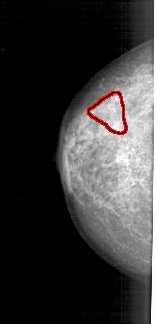

A_1723_1.LEFT_CC

LEFT_CC LINES 4201 PIXELS_PER_LINE 2026 BITS_PER_PIXEL 12 RESOLUTION 43.5 OVERLAY

FILE: A_1723_1.LEFT_CC.OVERLAY

TOTAL_ABNORMALITIES 1

ABNORMALITY 1

LESION_TYPE CALCIFICATION TYPE PLEOMORPHIC DISTRIBUTION SEGMENTAL

ASSESSMENT 4

SUBTLETY 3

PATHOLOGY MALIGNANT

TOTAL_OUTLINES 1

BOUNDARY